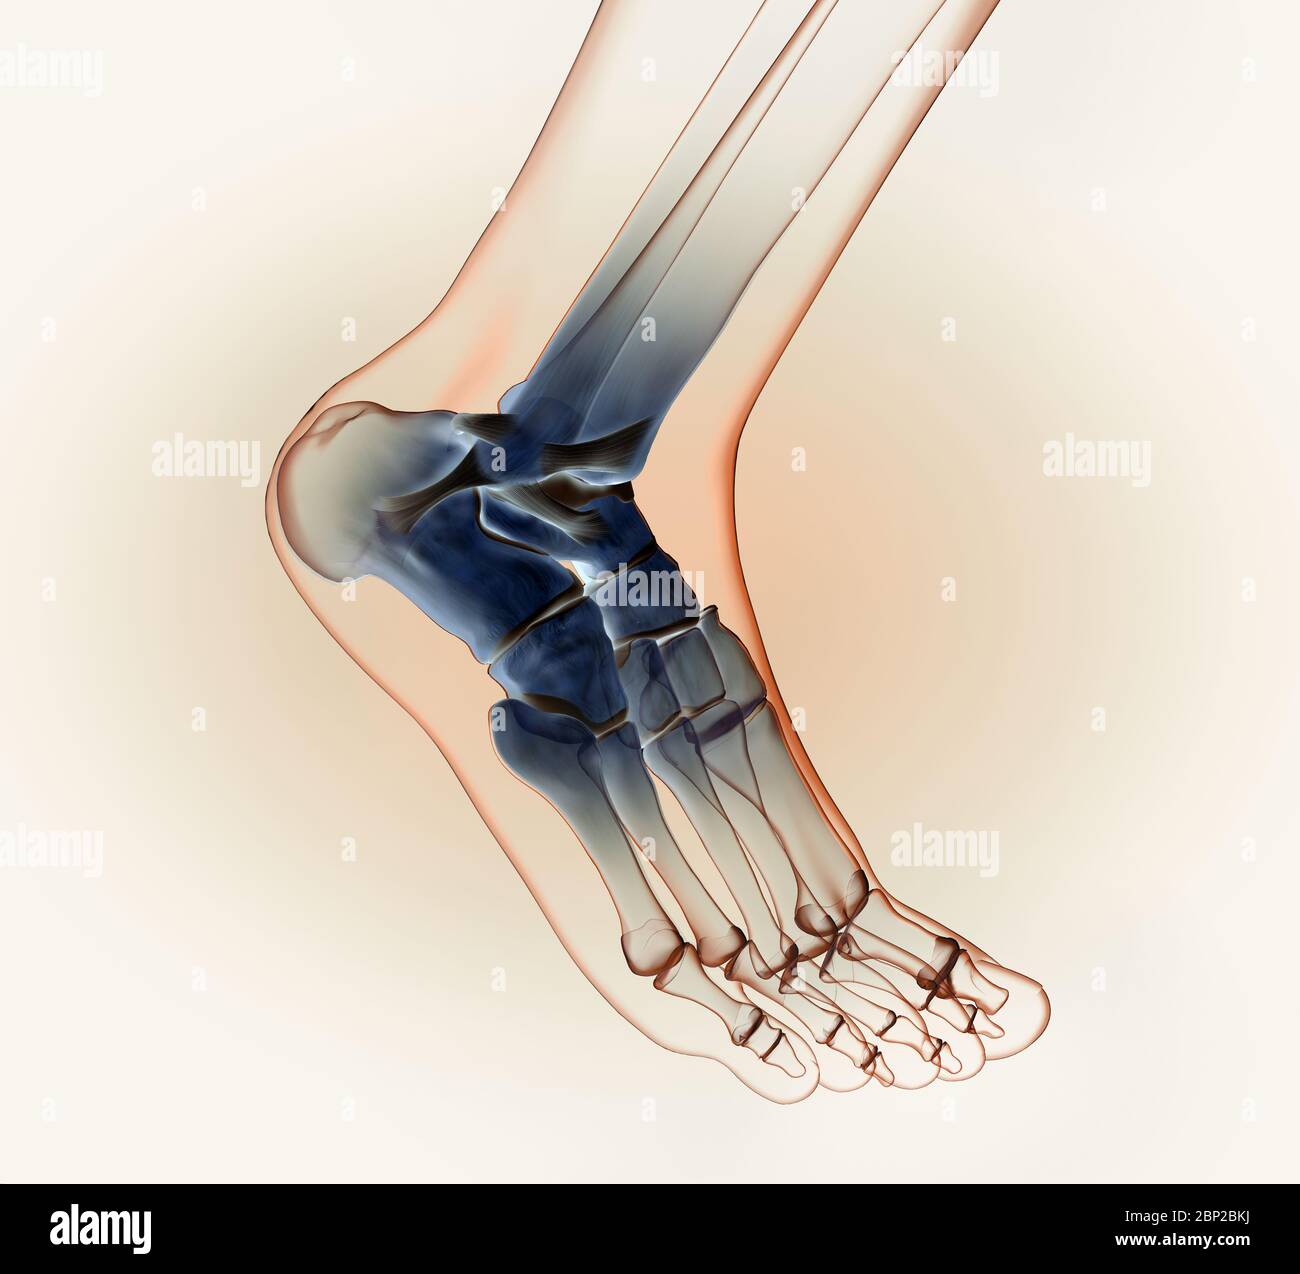

3D illustration showing of a ankle joint with bones, ligaments and articular capsule Stock Photohttps://www.alamy.com/image-license-details/?v=1https://www.alamy.com/3d-illustration-showing-of-a-ankle-joint-with-bones-ligaments-and-articular-capsule-image357782943.html

3D illustration showing of a ankle joint with bones, ligaments and articular capsule Stock Photohttps://www.alamy.com/image-license-details/?v=1https://www.alamy.com/3d-illustration-showing-of-a-ankle-joint-with-bones-ligaments-and-articular-capsule-image357782943.htmlRF2BP2BP7–3D illustration showing of a ankle joint with bones, ligaments and articular capsule

3D illustration showing of a ankle joint with bones, ligaments and articular capsule Stock Photohttps://www.alamy.com/image-license-details/?v=1https://www.alamy.com/3d-illustration-showing-of-a-ankle-joint-with-bones-ligaments-and-articular-capsule-image357782870.html

3D illustration showing of a ankle joint with bones, ligaments and articular capsule Stock Photohttps://www.alamy.com/image-license-details/?v=1https://www.alamy.com/3d-illustration-showing-of-a-ankle-joint-with-bones-ligaments-and-articular-capsule-image357782870.htmlRF2BP2BKJ–3D illustration showing of a ankle joint with bones, ligaments and articular capsule